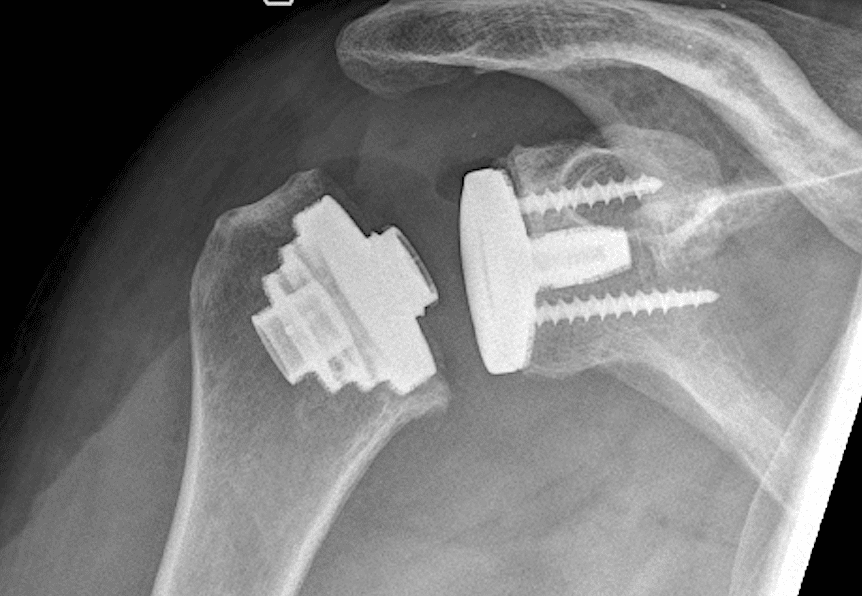

Eine Schulterprothese ersetzt das natürliche Schultergelenk – teilweise (Teilprothese) oder vollständig (Totalendoprothese). Je nach Schädigung von Knochen, Knorpel und Sehnen kommen unterschiedliche Prothesenformen zum Einsatz:

• Anatomische Schulterprothese: Nachbildung des natürlichen Gelenks

• Inverse (umgekehrte) Schulterprothese: Besonders geeignet bei Sehnenschäden (Rotatorenmanschettenruptur)

• Hemiprothese: Ersatz nur des Oberarmkopfes

Es gibt zwei Arten von Schulterprothesen, bestehend aus je mindestens drei Komponenten.

Die anatomische Schulterprothese besteht aus

1. Einem Anteil des Oberarmes

2. Einem künstlichen Oberarmkopf

3. Und einer Gelenkpfanne

Die inverse Schulterprothese ebenfalls aus

1. Einem Oberarmanteil

2. Einem Gelenksanteil

3. Sowie einer in die Gelenkpfanne geschraubte Glenosphäre

Erstere, anatomische, wird vorallem eingesetzt bei der primären Arthrose mit erhaltener Rotatorenmanschette, leztere, inverse, bei ausgedehnten Gelenkszerstörungen und Rotatorenmanschettendefekten.

Beide Prothesen könne sowohl in einer biologischen Variante (Einwachsen den bestehenden Knochen) sowie in einer zementierten Variante (Fixierung der Prothese im Knochen durch Knochenzement) verwendet werden.